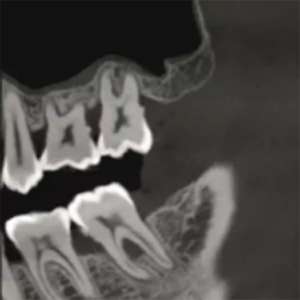

High-Resolution Dental CBCT Imaging

The system achieves image resolutions up to 2.0 lp/mm with a voxel size range of 0.05 – 0.25 mm.

Its 0.5 mm small focus tube guarantees smooth, stable, and reliable scans.

Furthermore, the high-definition image output ensures accurate diagnosis and confident treatment planning.

0.5mm small focus tube ensures outstanding image quality.

Resolution up to 2.0lp/mm, voxel size of 0.25~0.05 mm optional.

Furthermore, Panoramic Images are Reconstructed from 3D Dental CBCT data for clearer visualization